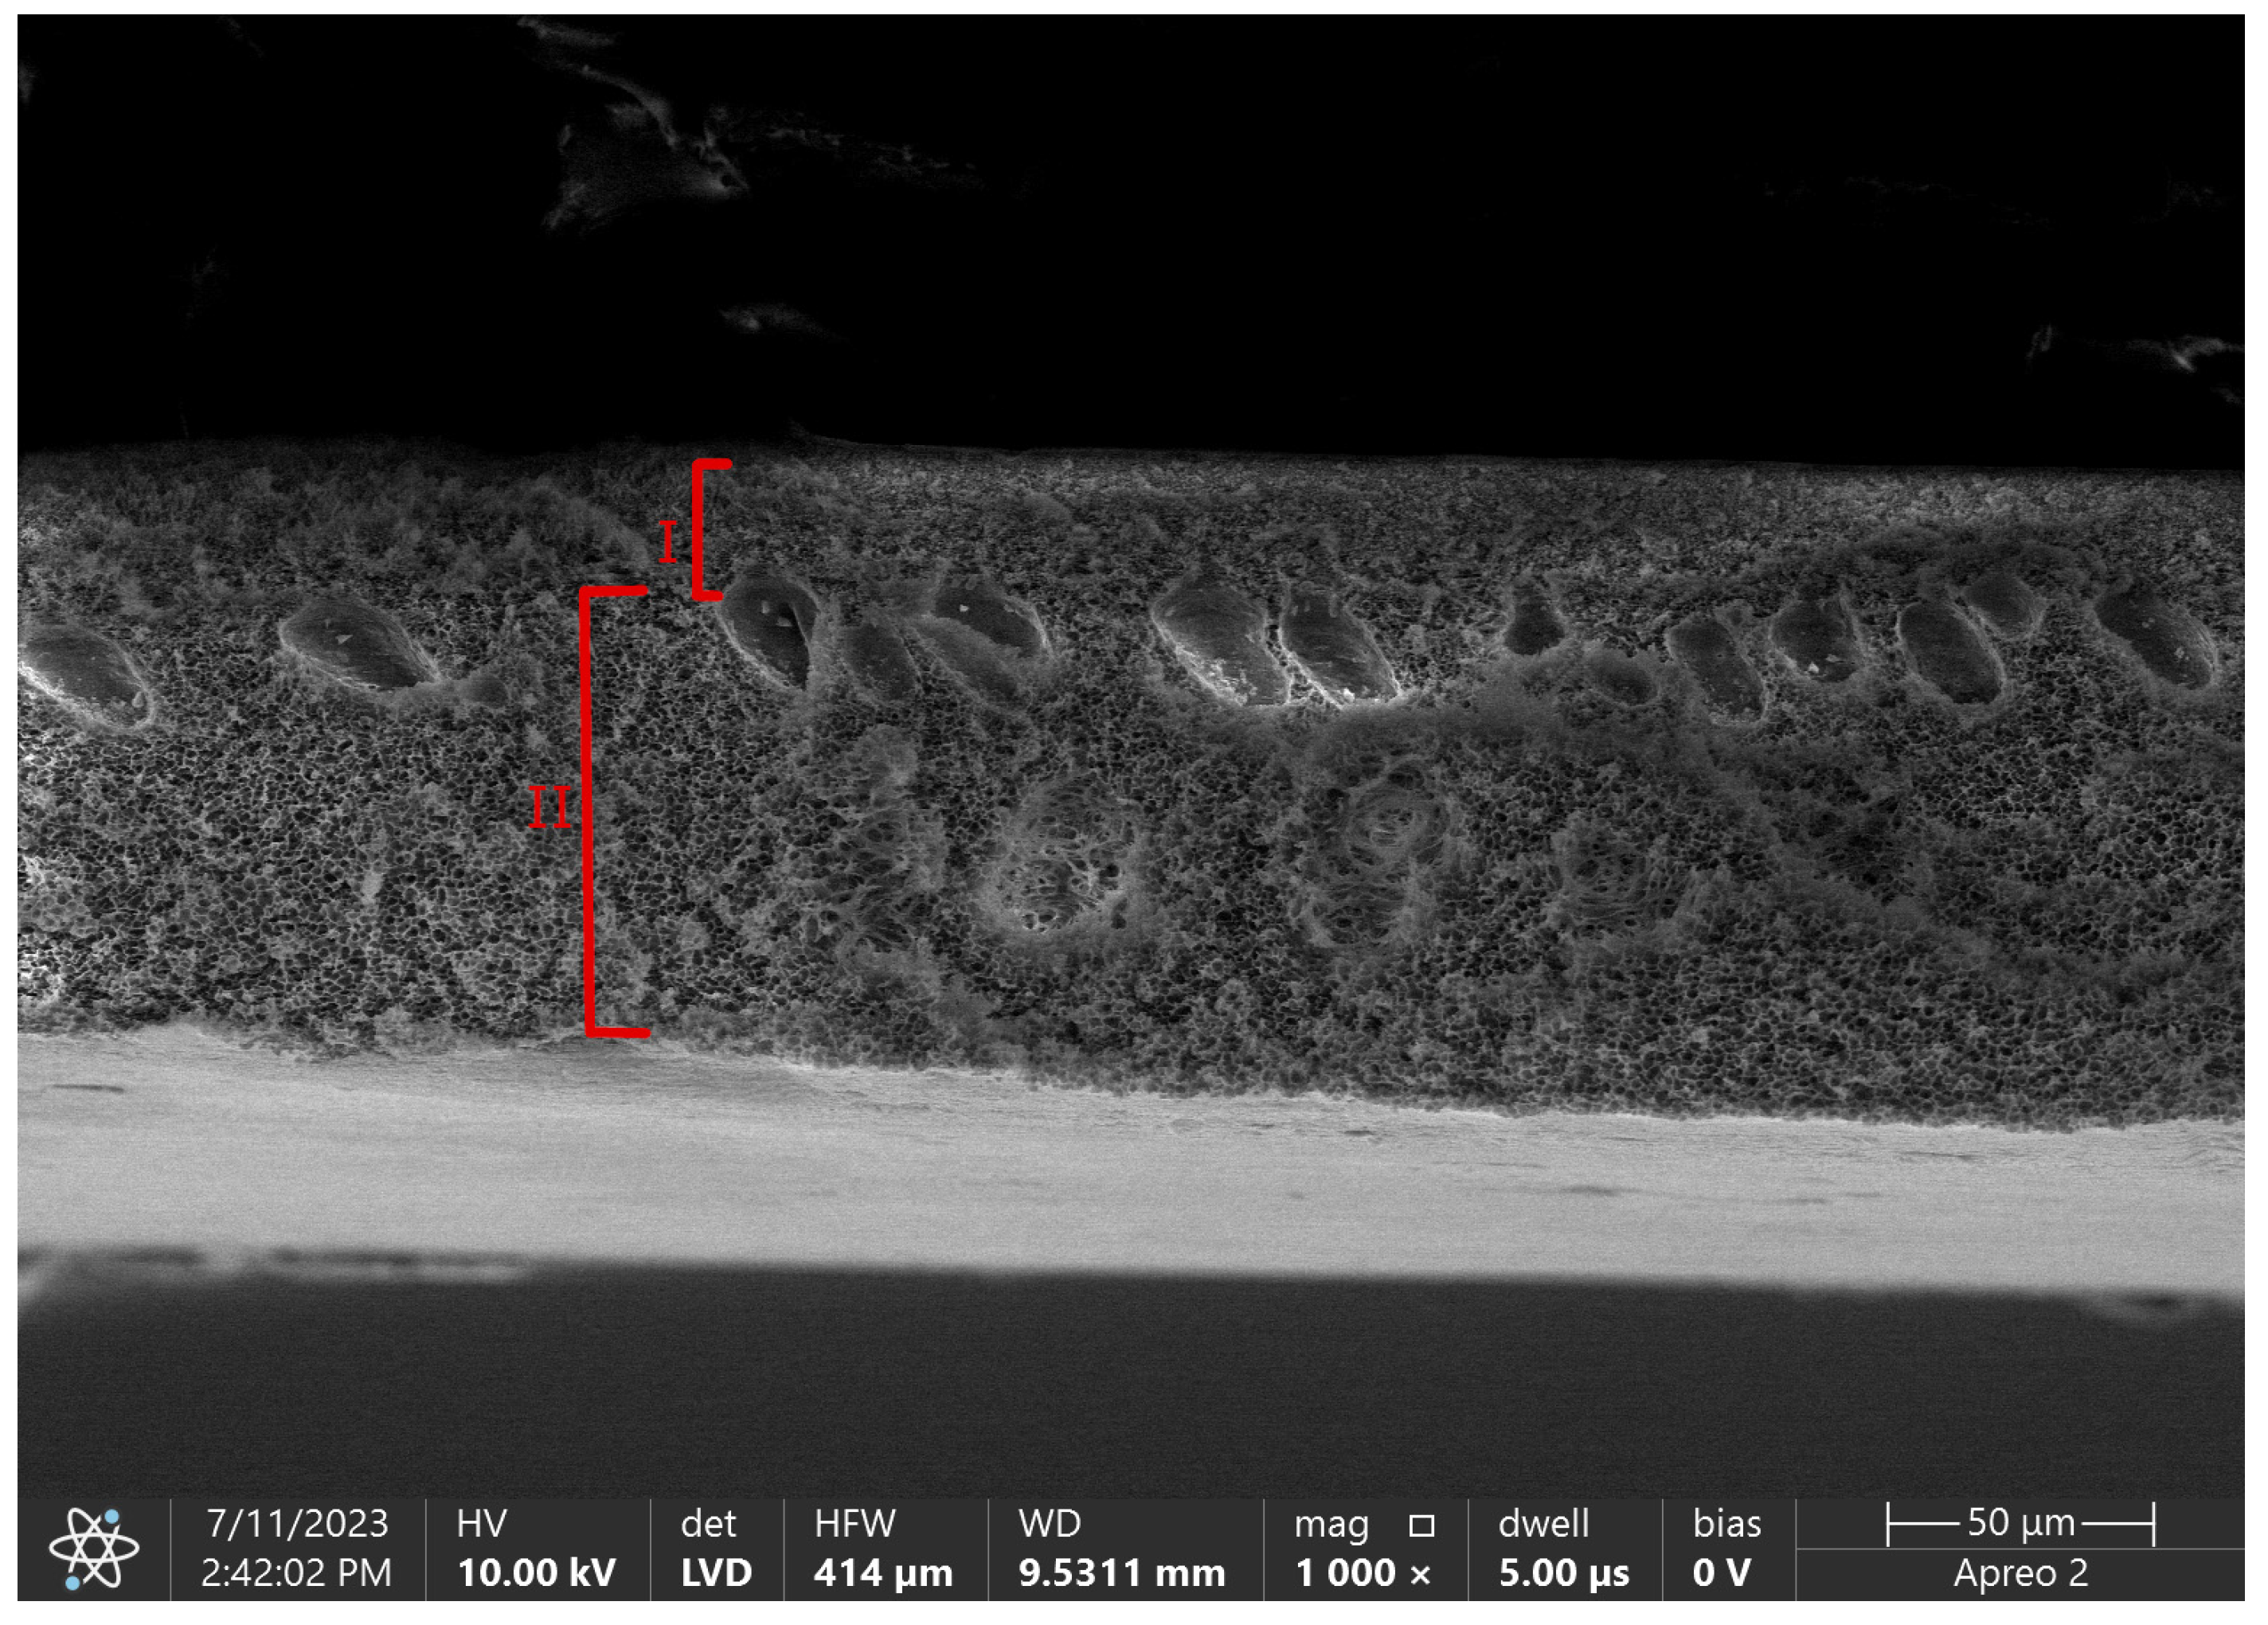

By phase inversion technique we are able to obtain asymmetric membranes with complicated porous structure divided into a skin layer and a support layer [43]. A skin layer, also called an active layer, is a blood-contacting side. Its thickness is a determinant of diffusion efficiency, with an inverse relationship between these two parameters [46]. The size of pores in this layer is also an eliminating factor for the size of removed molecules. The role of a support layer is to provide mechanical strength for the layer above, but also for the whole hollow fiber structure that needs to withstand high pressure differences during CRRT therapy. Figure 4. shows difference in porosity between those layers in pure polysulfone flat sheet membrane.

Figure 4. SEM micrograph of flat sheet pure polysulfone membrane with marked layers. I-skin layer, II- support layer. Own photo.